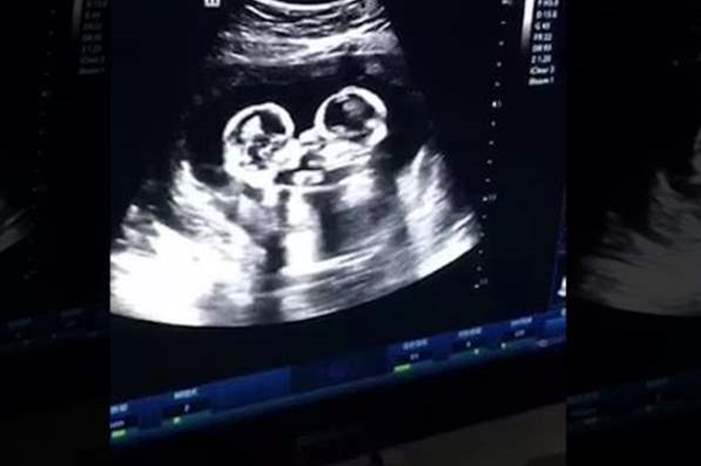

الوكيل الاخباري - يبدو أن المنافسة بين الأشقاء تبدأ حتى قبل الولادة، على الأقل هذا ما يظهره فيديو لمسح بواسطة الموجات فوق الصوتية "ألترا ساوند" لطفلتَيْن توأم في رحم أمّهما.

فقد أظهر فيديو لمسح بالموجات فوق الصوتية "ألترا ساوند" توأمين اثنتين التقط في عيادة نسائية في أحد مستشفيات الصين وهما توجهان اللكمات إلى بعضهما بعضا، بحسب ما ذكرت صحيفة الـ "صن" البريطانية.

وفي الإنترنت اشتهرت التوأم الأثنتان باسمي "تشيري" و"ستروبري"، أي "كرزة" وفراولة"، وشوهدتا، في الفيديو الذي التقط العام الماضي وأفرج عنه مؤخراً، من خلال "الألتراساوند" وهما تتلاكمان.

وقال والد التوأم "تاو"، في تصريح للصحف الصينية المحلية، إنه هو من قام بتصوير اللقطات أثناء المسح بالموجات الصوتية لرحم الأم، وذلك في أحد مستشفيات مدينة ينتشوان وسط الصين.

وأوضح الأب، البالغ من العمر 28 عاماً، أنّه لم يصدق عينيه عندما شاهد التوأم وهما توجهان اللكمات إلى بعضهما بعضا.